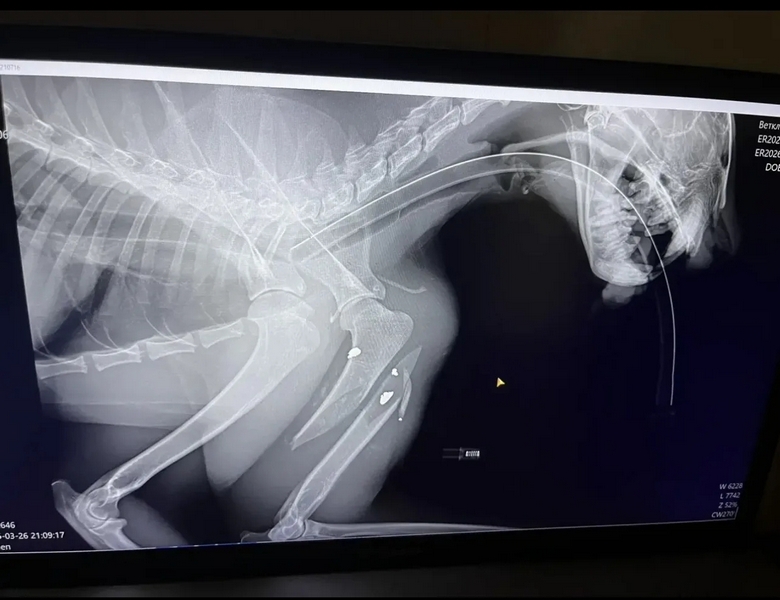

«Специалисты пришли к выводу, что рысь некоторое время назад стала жертвой ДТП, - рассказала директор «Легенды» Наталия Иванова. - У нее сломаны резцы, отсутствует клык, травма глаза, переломы передней и задней лап».

Кроме набора веса, рыси предстоит еще несколько операций в «Госпитале дикой природы». После этого животное вернется в «Легенду» - животное не предназначено к выпуску, поскольку полная реабилитация, в том числе полное восстановление зрения, уже невозможно.